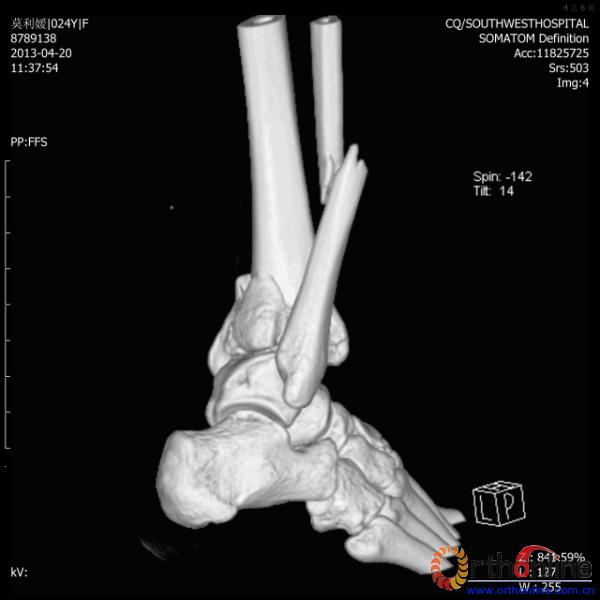

伤员和家属迅速赶到西南医院,10点关节外科段小军副教授查看伤员后急诊收入院,拍摄X片和急诊行三维CT重建检查,提示踝关节创伤严重,出现三踝骨折伴胫距关节脱位,需要急诊手术治疗。随后段教授与正在四川成都参加“汶川地震5周年灾害医学救治研讨会”的杨柳主任联系,进一步完善救治方案。地震当晚,段教授为该伤员进行急诊手术,手术顺利对复杂骨折进行了解剖复位,有效的钢板螺钉固定。术后伤员的疼痛明显缓解,复查X片,踝关节结构恢复满意。

患者术前CT(一)